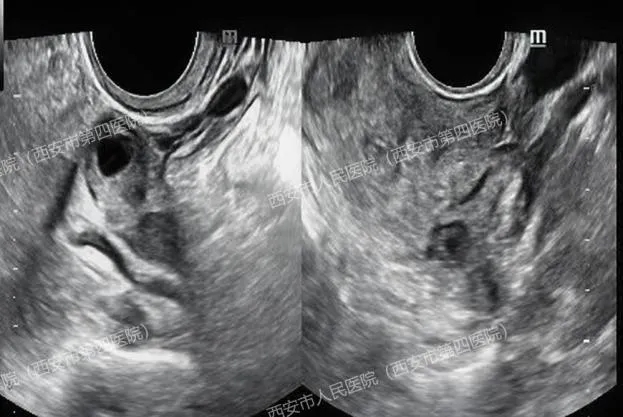

(上图腔内超声显示宫腔内未见孕囊,下图显示右侧卵巢小囊肿)

(肝右叶有一个47x35mm的囊实性占位,附件区包块影像显示为卵巢巧克力样囊肿,并非妊娠囊)